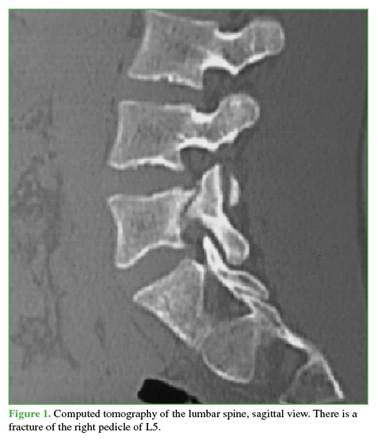

Anteroposterior, lateral, and oblique radiographs of the lumbar spine showed sclerosis of the right pedicle and left-sided spondylolysis at the level of the fifth lumbar vertebra. CT scan revealed, in addition to the findings mentioned above, a discontinuity in the right pedicle, with sclerotic and hypertrophic margins (Figures 1 and 2). Magnetic resonance imaging demonstrated edema in the lumbar pedicle (Figures 3 and 4).

A common feature of pediculolysis is sclerosis of the pedicle, although it remains unclear whether this represents an adaptive phenomenon prior to the fracture or a consequence of it.9 This unilateral sclerosis gives the vertebra an asymmetric appearance on radiological imaging. Computed tomography (CT) undoubtedly allows for better assessment of the lesion, differential diagnosis, monitoring of progression, and, in some cases, therapeutic planning. Characteristic CT findings include a radiolucent line of discontinuity with sclerotic and hypertrophic margins.4 Magnetic resonance imaging (MRI) has high sensitivity for diagnosing these lesions. While it may or may not reveal the fracture line at the pedicle level, it does demonstrate associated edema, which appears hypointense on T1-weighted sequences and hyperintense on T2-weighted sequences.3,4